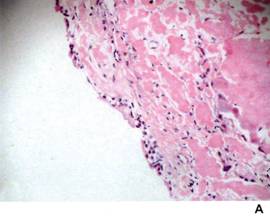

淀粉样物质主要是多糖蛋白复合体,其组织切片在光镜下呈无定型的均匀的嗜伊红性物质,用刚果红染色偏光镜下观察可见特异的苹果绿色荧光。电镜下可见两种不同的结构,主要成分为大小约10nm的原纤维,另一为切面呈五角形中空的杆状物质(P成分),后者的化学物理特性在所有的淀粉样变病中都是一致的,原纤维则由多肽链组成,一般耐蛋白水解酶消化,因而可形成淀粉样沉淀,破坏或取代正常组织。见图1A,B,C。

(1)心脏:镜下可见淀粉样物质沉积于心肌纤维间,通常乳头肌病变广泛,传导系统也可有同样病变并有纤维化,冠状动脉和静脉内、外膜常见有淀粉样物质沉积而导致管腔狭窄。